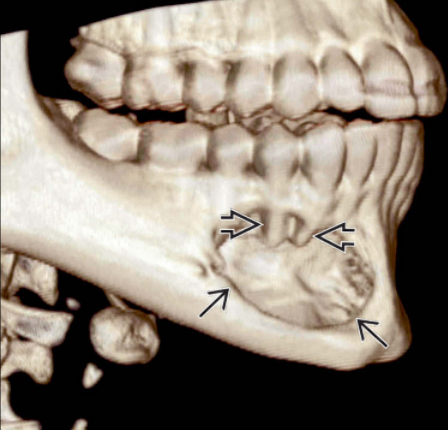

3.4. Στατική ή Ιδιοπαθής οστική κύστη (κύστη του Staffne)

Η στατική οστική κύστη είναι μια ανατομική παραλλαγή της οπίσθιας γλωσσικής επιφάνειας της κάτω γνάθου, που φαίνεται να ομοιάζει σε κύστη κατά την ακτινογραφική εξέταση. Το εντύπωμα αυτό της κάτω γνάθου πιστεύεται ότι είναι μια ανατομική παραλλαγή, μολονότι όλες οι αναφερόμενες περιπτώσεις εντοπίζονται σε ενήλικες, συχνότερα δε σε άντρες. Οι βλάβες αυτές ανευρίσκονται συχνότερα αμφοτερόπλευρα, σπανιότερα εντοπίζονται σε θέση εγγύτερα του πρώτου γομφίου της κάτω γνάθου.

Η αιτία είναι άγνωστη, μολονότι μερικοί έχουν προτείνει ότι η βλάβη οφείλεται σε παγίδευση σιελογόνου αδένα ή μαλακών μορίων κατά την ανάπτυξη της κάτω γνάθου.

Η βλάβη είναι ασυμπτωματική και συχνά ανακαλύπτεται τυχαία κατά τη λήψη πανοραμικής ακτινογραφίας. Η παρουσία αδενικού ιστού εντός της βλάβης επιβεβαιώνεται με σιελογραφία.